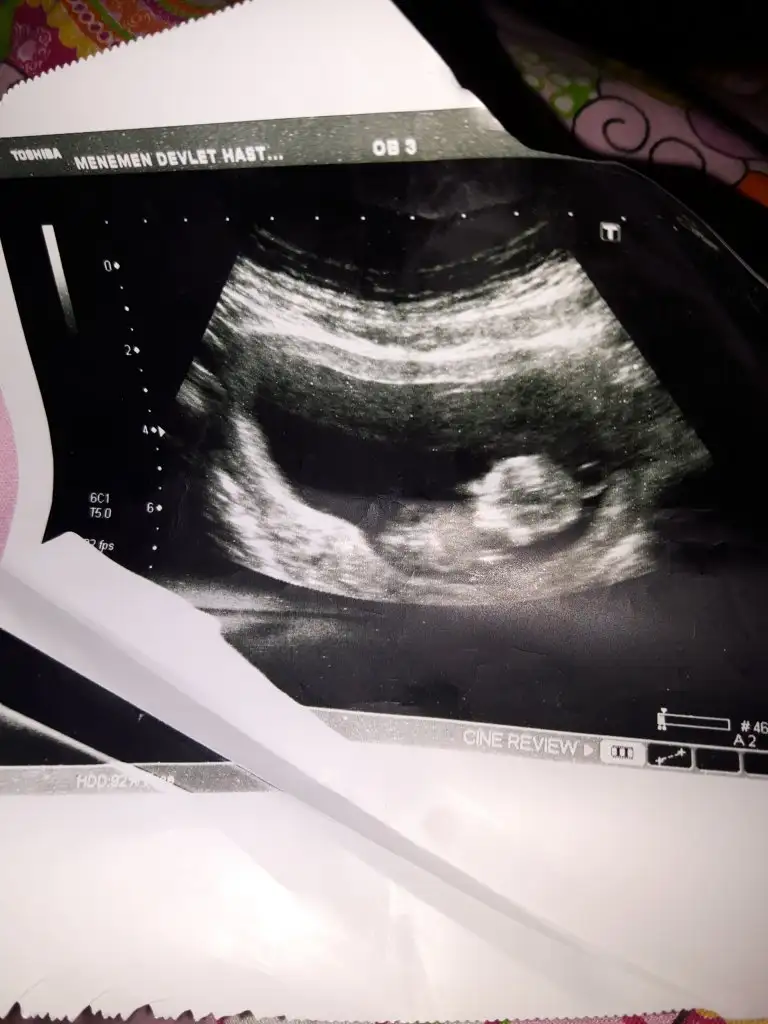

Selam 12 haftalığına sizce cinsiyet nedir erken ama ölücem meraktan önce afiyetle gelişmesi tabiiki...

Eklentiler

• 20191122_233813.webp

37 KB · Görüntüleme: 60